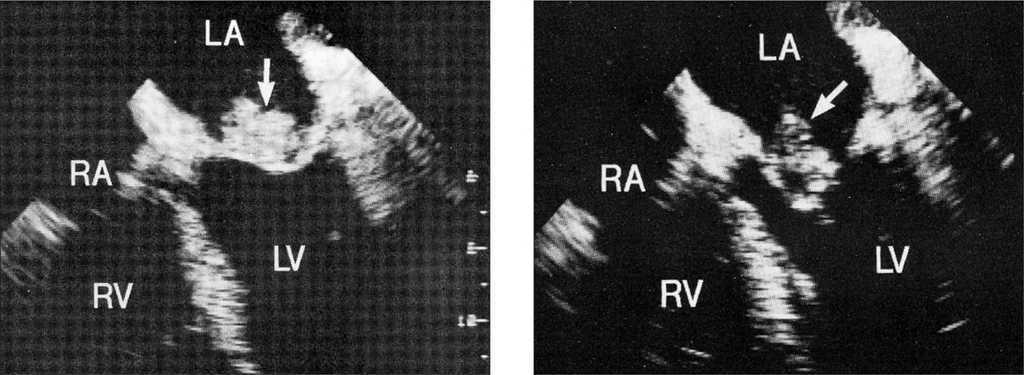

Un paciente con trisomía 18 y cardiopatía murió súbitamente antes de realizar el examen ultrasonográfico. La ecocardiografía fue positiva en 36 de los 55 pacientes que pasaron un examen (65,4 %). Durante el período que fue utilizada la ecocardiografía transesofágica, hubieron 28 casos de endocarditis y esa técnica fue utilizada en el 46,4 % de los pacientes. En el momento del diagnóstico de endocarditis, las anomalías ecocardiográficas se localizaron en el lado derecho del corazón en 11 pacientes y en el lado izquierdo en 18. En varios casos, las vegetaciones no estaban presentes en el estudio inicial, pero fueron observadas en los exámenes posteriores. Presentaban una vegetación evidente 31 pacientes. Tres pacientes presentaban vegetación en dos válvulas. La válvula mitral (fig. 2) fue la más frecuentemente afectada (13 casos), pero se encontraron anomalías en otras estructuras, la válvula aórtica (5 casos) (fig. 3), el sinus coronario (un caso), la válvula tricúspide (6 casos), la aurícula derecha (4 casos) y la válvula pulmonar (un caso). En 4 pacientes, las anomalías se encontraron localizadas en la comunicación interventricular. Los 6 niños sanos presentaron las anomalías solamente localizadas en el lado izquierdo del corazón.

Figura 2. Vegetación en la válvula mitral. RA: aurícula derecha; LA: aurícula izquierda; RV: ventrículo derecho; LV: ventrículo izquierdo.